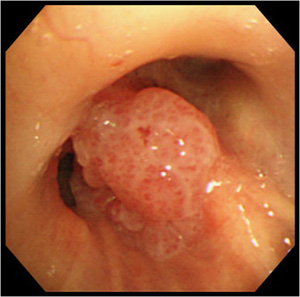

- 2)扁平上皮がん(へんぺいじょうひがん)

太い気管支にできやすく血痰や咳などの症状を生じやすい肺がんです。喫煙が発症に大きく影響しています。

気管支内に発生した扁平上皮がん

気管支鏡で観察した所見 - 3)大細胞がん(だいさいぼうがん)